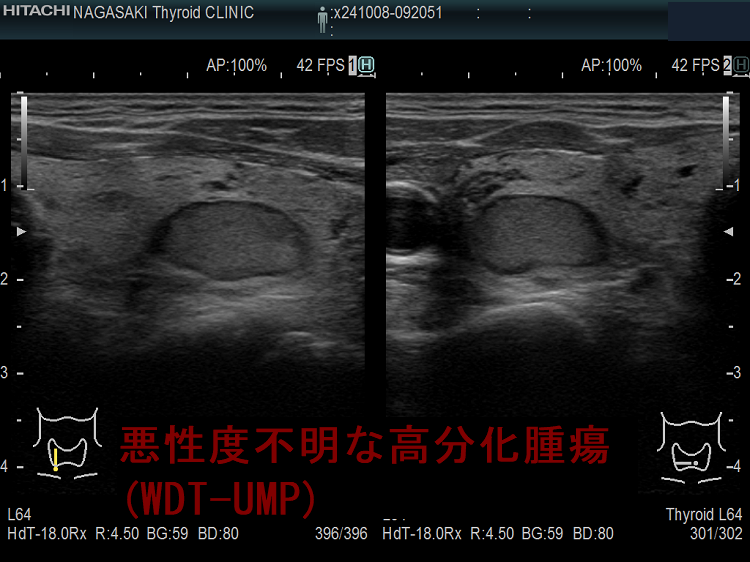

悪性度不明な高分化腫瘍(WDT-UMP);超音波(エコー)画像から判るように、良性濾胞腺腫よりも、腺腫様結節や濾胞型甲状腺乳頭癌に近い見え方です。